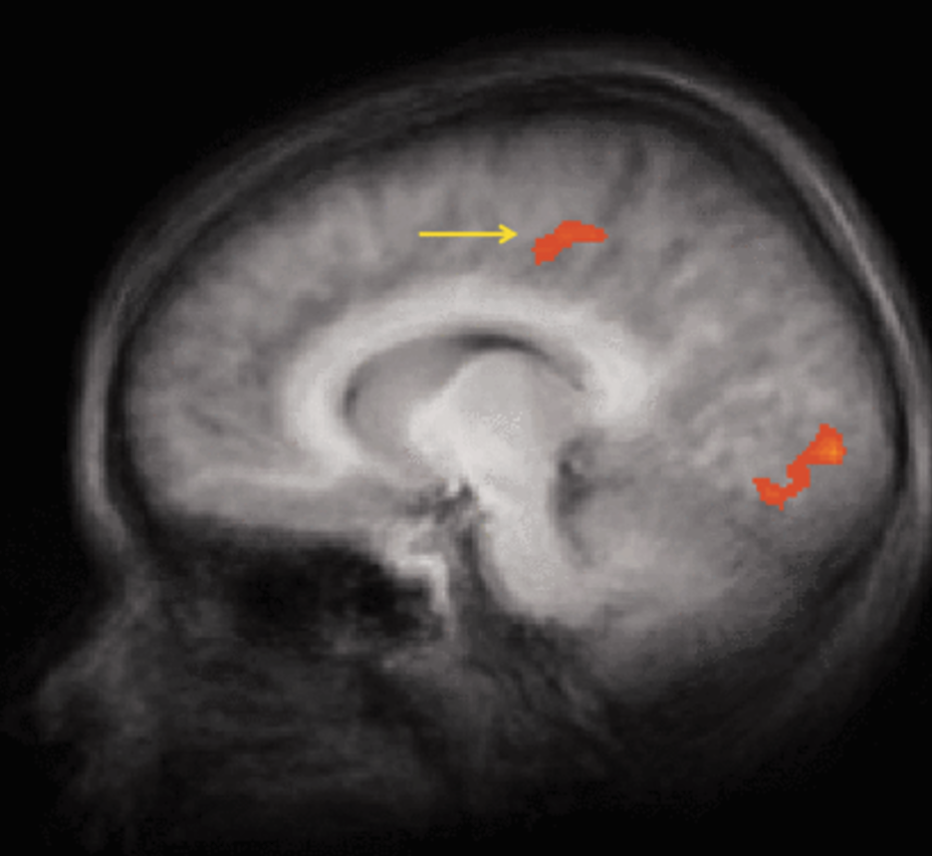

From Relapse to Recovery: How Neuromodulation Techniques Could Revolutionize Addiction Treatment

Substance use disorder (SUD) claims an estimated 67,000 lives annually in Canada, highlighting the devastating impact of the drug epidemic (CAMH 2025). SUD is a chronic illness that causes symptoms of impaired judgement, impulsiveness, drowsiness, nausea and vomiting, and mood changes. These symptoms can lead to significant impairments in health, social function, and voluntary substance…